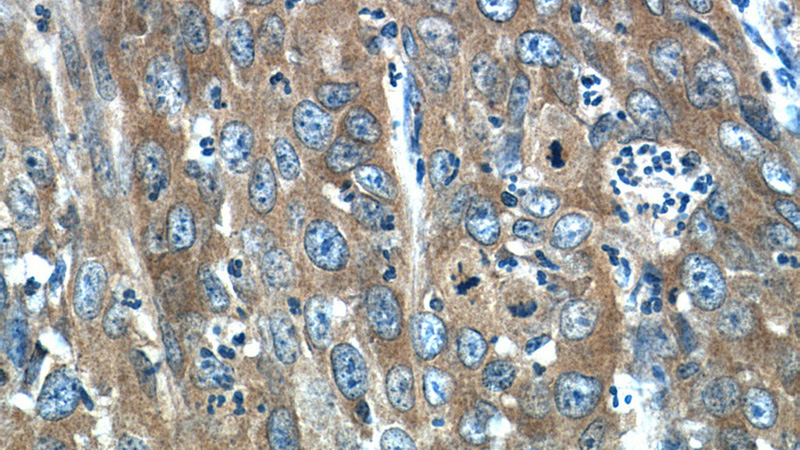

Immunohistochemistry of paraffin-embedded human cervical cancer tissue slide using Catalog No:112696(MMP1 Antibody) at dilution of 1:200 (under 40x lens)